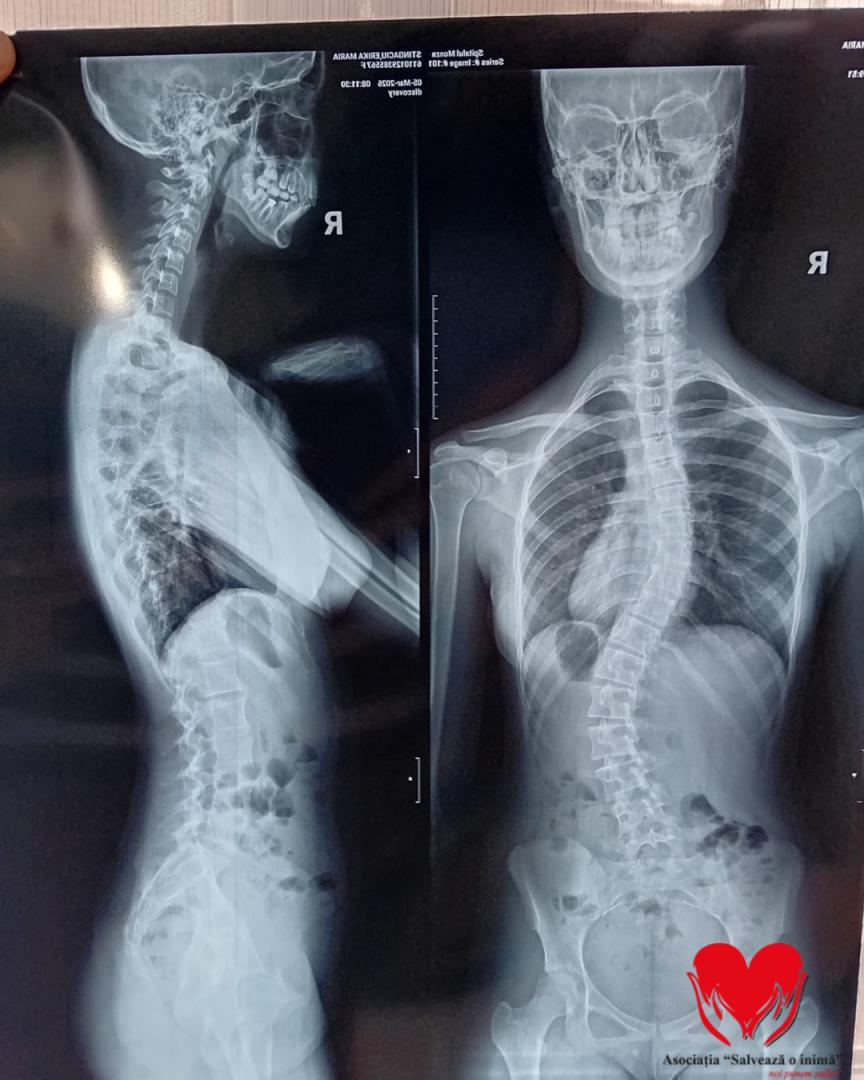

La doar 15 ani, Erika se confruntă cu un diagnostic sever de scolioză dorsolombară progresivă. Adolescenta spune că își simte spatele deformându-se tot mai mult cu fiecare zi. Medicii spun că singura șansă a fetei este o intervenție chirurgicală complexă, însă costul acesteia depășește cu mult posibilitățile familiei.

Până în urmă cu doi ani, Erika era un copil obișnuit, cu planuri simple și o copilărie trăită firesc. Totul s-a schimbat în februarie 2024, când, în urma unui consult aparent banal, medicul a observat o asimetrie la nivelul umerilor. Investigațiile ulterioare au condus la stabilirea diagnosticului de scolioză idiopatică lombară, iar de atunci viața ei a devenit o luptă continuă pentru a încetini evoluția afecțiunii.

A urmat zilnic ședințe de kinetoterapie, a purtat un corset rigid tip Cheneau timp de 23 de ore din 24 și a trecut prin multiple consultații și investigații în centre medicale din țară. În ciuda tuturor eforturilor, evoluția a continuat, iar în februarie 2026, în urma unui nou control, medicii au confirmat caracterul progresiv al scoliozei și necesitatea unei intervenții chirurgicale.

În prezent, Erika continuă să poarte corsetul zilnic și să urmeze terapii, însă acestea nu mai pot opri evoluția deformării coloanei. Singura soluție rămasă este intervenția chirurgicală, care îi poate reda șansa la o viață fără durere și fără limitările actuale.